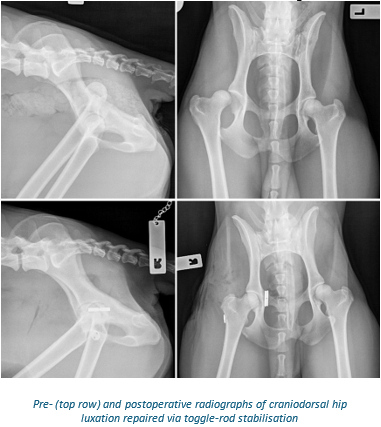

- Toggle rod stabilisation – this involves placing an anchor into the base of the acetabulum and using a braided suture to re-create the ligament of the femoral head that is passed through a bone tunnel in the femur. This is the treatment of choice for most traumatic hip luxations and some atraumatic hip luxations and is successful in 85-90% of cases.

Toggle-rod stabilisation requires 6-8 weeks of strict crate or room confinement while the damaged joint capsule and periarticular muscles repair. Radiographs will be performed after the recovery period to ensure the implants remain in place.

The outcome following toggle-rod stabilisation is excellent in most cases. Animals will develop a degree of osteoarthritis following any traumatic injury to a joint including hip luxation and, as such, life-long strategies to manage this will be important (weight control, exercise moderation, medical management).

Complications are uncommon following toggle-rod stabilisation; however, complications to be aware of are re-luxation (10-15%), infection (<5%) and implant irritation of soft tissues (rare).